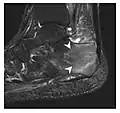

Figure 1: A 56-year-old woman presenting with left knee pain after a fall. (a) Initial anteroposterior radiograph was considered normal, however, subtle cortical disruption of the anterior rim of the medial tibial plateau, medial to the tibial spine, is noted (arrow). (b) Coronal T1-weighted MRI confirms the cortical disruption (arrow) and shows extensive fracture through the proximal tibia. (c) Coronal proton density-weighted image with fat saturation shows extensive edema in the subchondral bone. Note also hypersignal adjacent to the medial collateral ligament corresponding to a grade I sprain (arrowheads).[1]